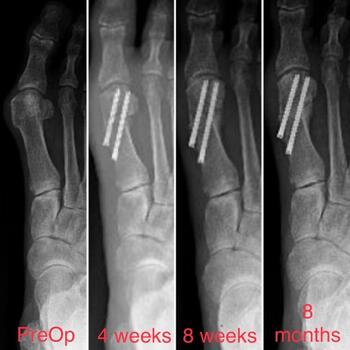

The surgeon may shift the capital fragment as much as necessary as long as there is some contact maintained between the metatarsal shaft and the head. It is possible to plan the amount of translation necessary on the preoperative X-ray, based on the position of the fibular sesamoid. In our experience, the lateral cortex of the metatarsal head should end up in a position just lateral to the fibular sesamoid on the preoperative X-ray. The gap between the lateral metatarsal head and metatarsal shaft will consolidate over time (see sixth and seventh photos above). A multitude of advanced options for fixation exist, including, but not limited to headless compression implants (see seventh and ninth photos above) and plate-intramedullary hybrid devices (see sixth photo above). Intramedullary devices do require a slightly larger incision for appropriate placement.

We have found success with immediate protected weight bearing in a short CAM walker boot. The lack of violation of the first MPJ capsule is the most advantageous portion of this procedure, as we avoid fibrosis or adhesions from the arthrotomy. We advise aggressive range of motion to tolerance daily for the first six weeks postoperatively. At four weeks, transition to a surgical shoe/may take place, and at six weeks, transition to supportive sneaker with accommodative insert. We typically obtain radiographs at four and eight weeks postoperatively. It is unnecessary to see bone consolidation before transition to sneaker as this secondary callus formation may lag behind the clinical union. We rely on patient symptoms and pain on palpation at the osteotomy site.